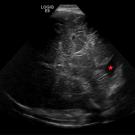

At 29 weeks of gestation, an enlarged cisterna magna of 1.1 cm had been discovered on fetal ultrasonography. Repeated measurement at 36 weeks had shown a dilation of 1.2 cm.